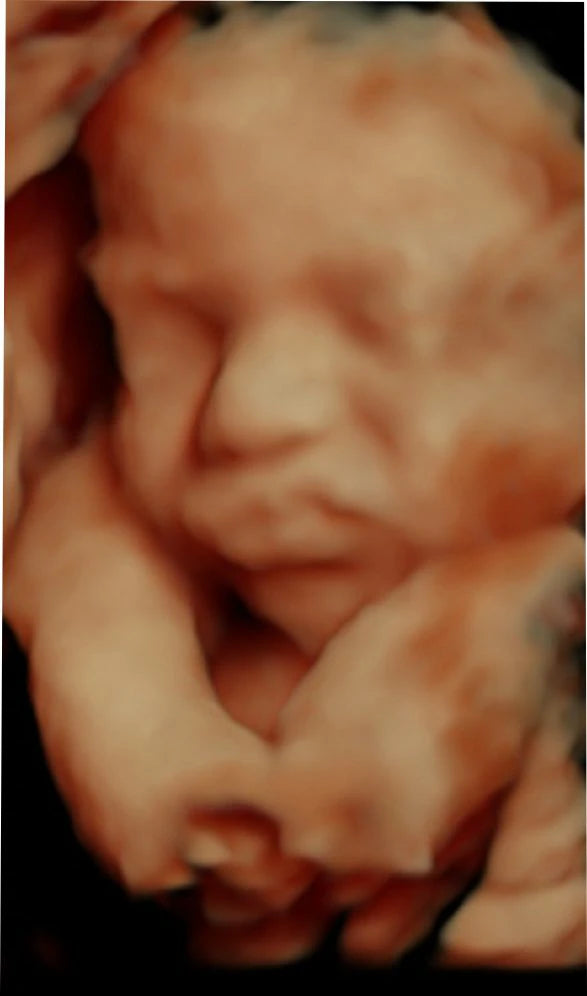

El ultrasonido obstétrico 4D HD es una innovadora técnica de imagenología que utiliza ondas de sonido para generar imágenes tridimensionales en alta definición de su bebé dentro del útero. Esta tecnología avanzada le permite observar los movimientos, gestos y rasgos faciales de su bebé en tiempo real, ofreciendo una experiencia emocionante y conmovedora durante el embarazo.

Imagen: Imagen de un bebé en el útero obtenida a través de un ultrasonido 4D HD.